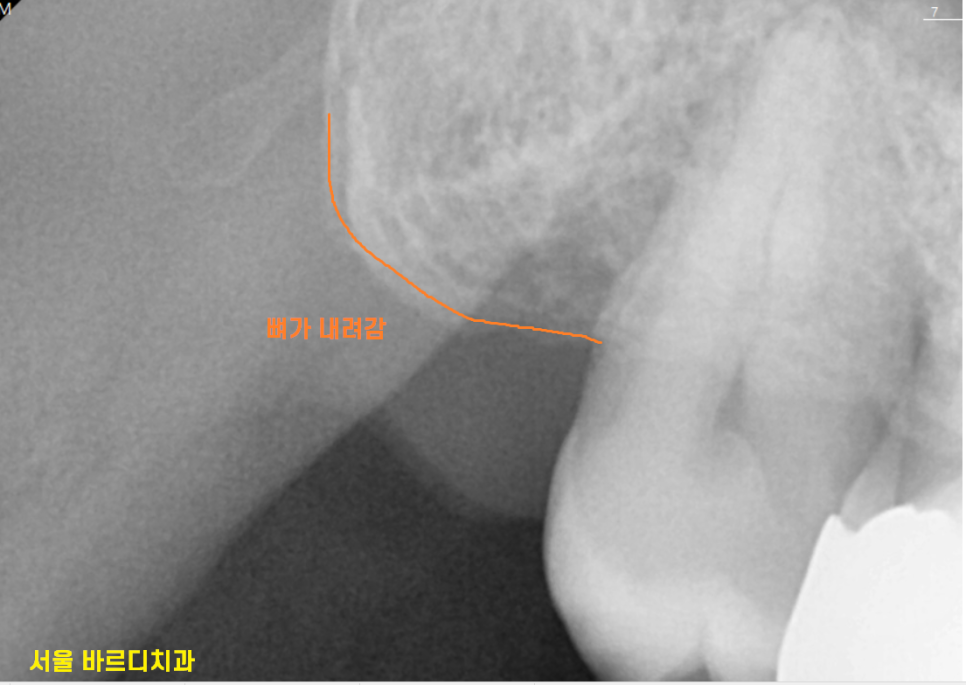

ct속 문제의 치아

뼈가 내려가다못하여

뿌리 염증까지 심해져서

이제 시기가 되었습니다.

놓아줄 시기가 되었다는 뜻이죠ㅠㅠ